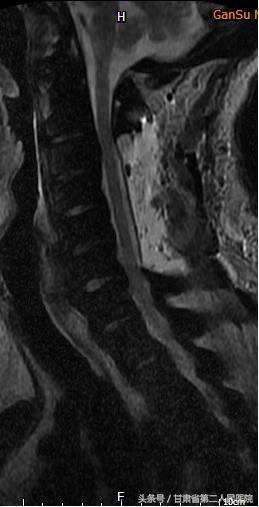

入院后行全脊柱X线、CT及MRI示:C3-6颈椎后纵韧带骨化引起的脊髓型颈椎病,并有严重的石骨症。

可见全身骨质密度均匀增高,符合石骨症表现

可见后纵韧带骨化

术前

术后